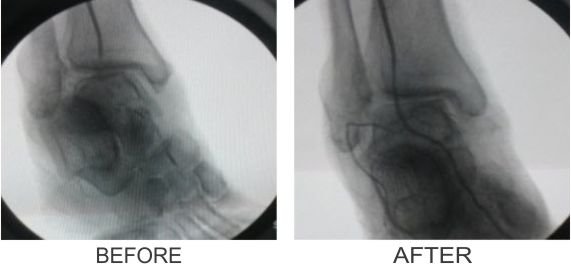

- Bypass: Often, long segment blockages or multilevel blockages are better dealt with by surgical bypass. Surgical bypass can be performed by using patients own vein or a synthetic graft and can be performed from the abdomen to the foot depending on the level and extent of arterial blockage. These procedures will not cure PAD, but they can improve the blood circulation to your legs and your ability to walk and thus prevent amputation.

Popliteo-Distal Bypass

Successful Treatments